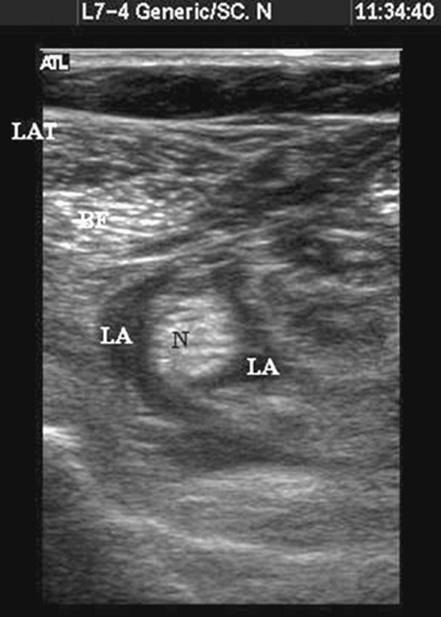

Once the needle tip lies adjacent to the nerve a muscle contraction can be elicited if preferred by slowly increasing nerve stimulator current until a twitch is seen (commonly less than 0.5 mA). Once nerve identity is confirmed, local anesthetic is incrementally injected. It is important to examine the spread of local anesthetic and ensure that spread is seen encircling the nerve (Fig. 41-5). Several needle positions may be needed to ensure adequate spread on either side of the nerve. The nerve can often be seen more easily to split into tibial and common peroneal components after injection (Fig. 41-6). The often-inadequate spread on injection with the needle in a fixed position may explain why many popliteal blocks with apparently excellent nerve stimulator endpoints fail even with large volumes of local anesthetic.

Figure 41-5. Sonogram of the popliteal fossa postinjection with local anesthetic seen encircling the nerve. N, nerve; BF, biceps femoris; Lat, lateral; LA, local anesthetic spread.